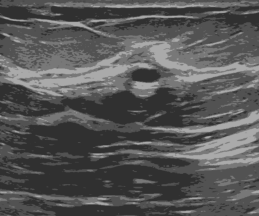

Refer to caption

(b) SLIC based Segmented Image (Benign Tumor)

Figure 4: Image Segmentation with SLIC

Here, the effect of SLIC based image segmentation is depicted in the Figure  4. In Figure  4(b), after applying SLIC, the image pixels sharing similarity in distribution are assigned into a particular cluster making the image easy to process and analyze. In this study, for implementation purposes, the OpenCV library has been used with a configuration of region size 20 of super-pixels, smoothing factor of 10 and 100 iterations per image.